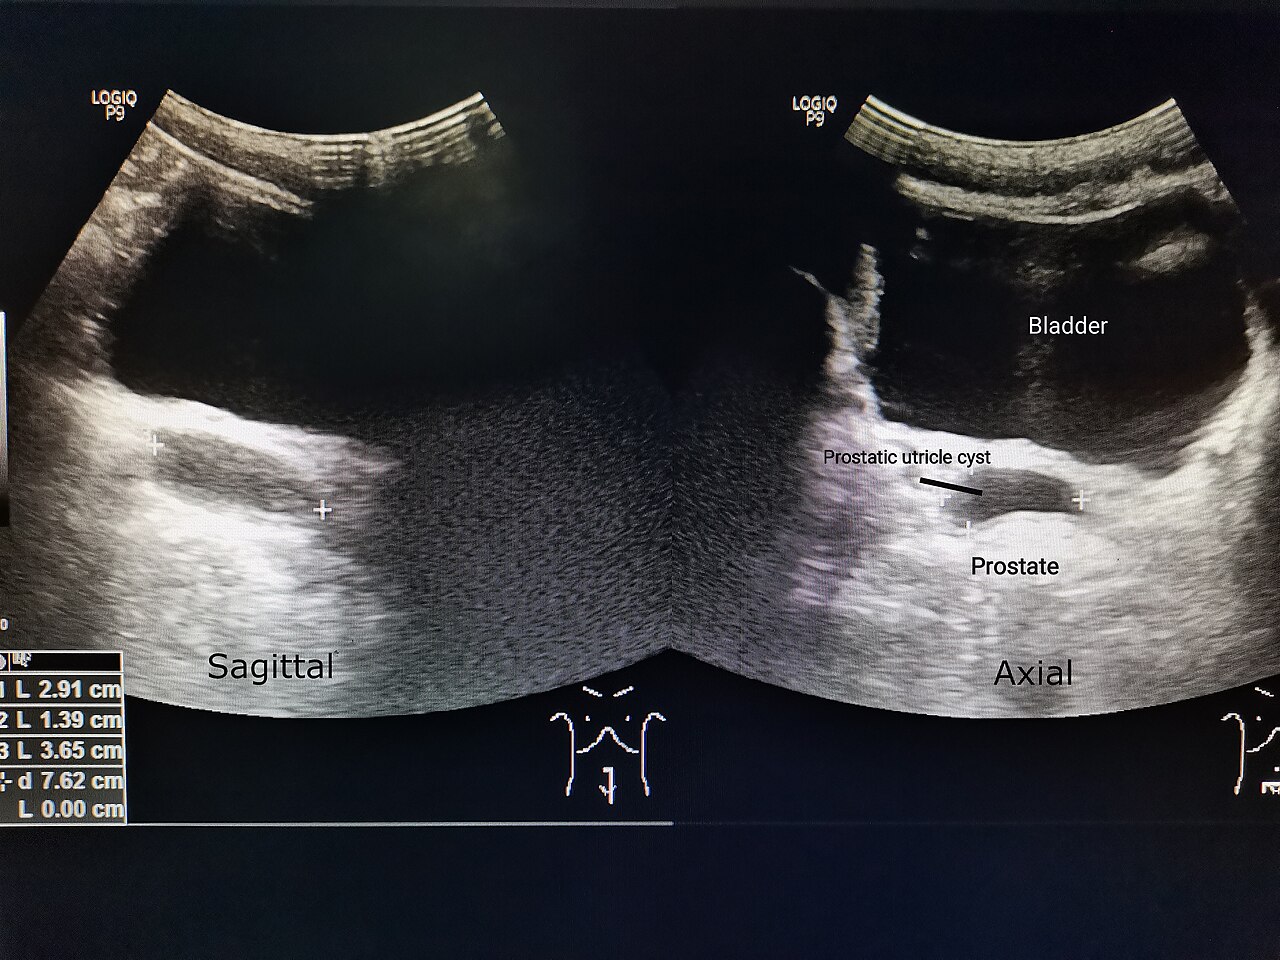

Prostate phantom for MRI with peripheral zone, transition zone, seminal vesicles, and suspicious PI-RADS lesion